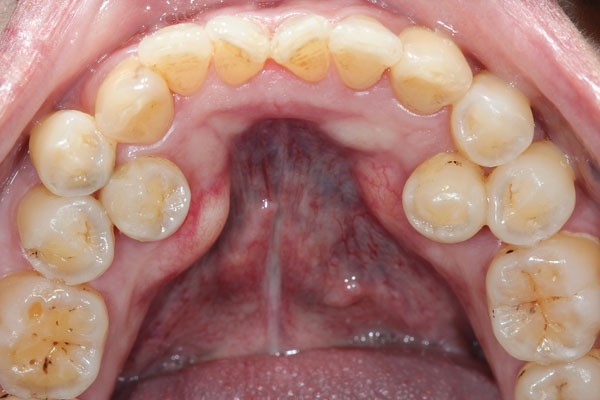

To explore these questions, Owaise Sharif and co-authors carried out a service evaluation of the joint dento-alveolar (JDA) clinic at the Croydon University Hospital. A prospective patient note analysis was carried out of 100 new patients attending between November 2014 and September 2015. Fifty-four percent of the patients were female, with the mean age 17 years. The most common anomalies referred were:

Supernumeraries (16%)

In addition to the service analysis described in part 1 of the BDJ series, in part 2 the authors provide an overview of common dental anomalies. Their definition, classification, aetiology and prevalence have been outlined along with their diagnosis and management. The aim of this is to increase awareness amongst practitioner's and help them formulate appropriate treatment plans. Part 1 of the series covers soft tissue anomalies, dentigerous cysts, transpositions and supernumerary teeth. Whereas part 2 focuses on impacted teeth, delayed and failed eruption, ankylosed incisors and infra-occluded deciduous molars.

Dental anomalies are often asymptomatic and may develop from an early age, the GDP therefore has a crucial role in early identification and management. In addition, dental anomalies often require onward referral to a specialist for management and so knowledge of potential management strategies will aid the GDP in counselling patients.